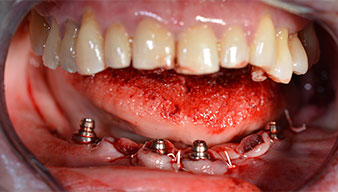

Para la planificación y la minimización del riesgo, se realizó una tomografía volumétrica tridimensional (TVD, Planmeca) que mostró que la calidad y la cantidad del tejido óseo era suficiente para la intervención quirúrgica y el tratamiento inmediato con el método Fast & Fixed. Siguiendo el protocolo de este método, se insertaron los implantes en la región de las piezas 35, 32, 42 y 45. Debido a la inclinación de hasta 45 grados de los implantes distales, el perfil de emergencia se desplazó hacia posterior y se generó un mayor polígono de soporte (fig. 3).

Para compensar la divergencia de los implantes distales, se atornillaron pilares acodados (35 grados) de forma que los perfiles de emergencia de todos los implantes quedaran en la posición más vertical posible en relación con la mordida. Este paso es necesario para poder atornillar de forma oclusal el tratamiento provisional y, posteriormente, el definitivo (figs. 15 y 16).